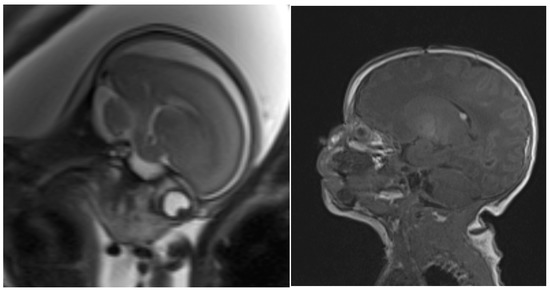

2. Case Description